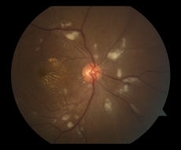

Fotografía de fondo de ojo derecho centrada en el nervio óptico, que muestra múltiples manchas algodonosas y exudados maculares en una configuración de estrella que se irradia alrededor de la fóvea

Cortesía de Angie Wen MD, profesora adjunta, New York Eye and Ear Infirmary, Nueva York; utilizado con permiso